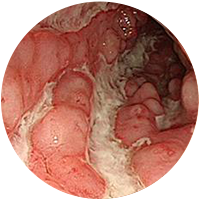

크론병

궤양성대장염